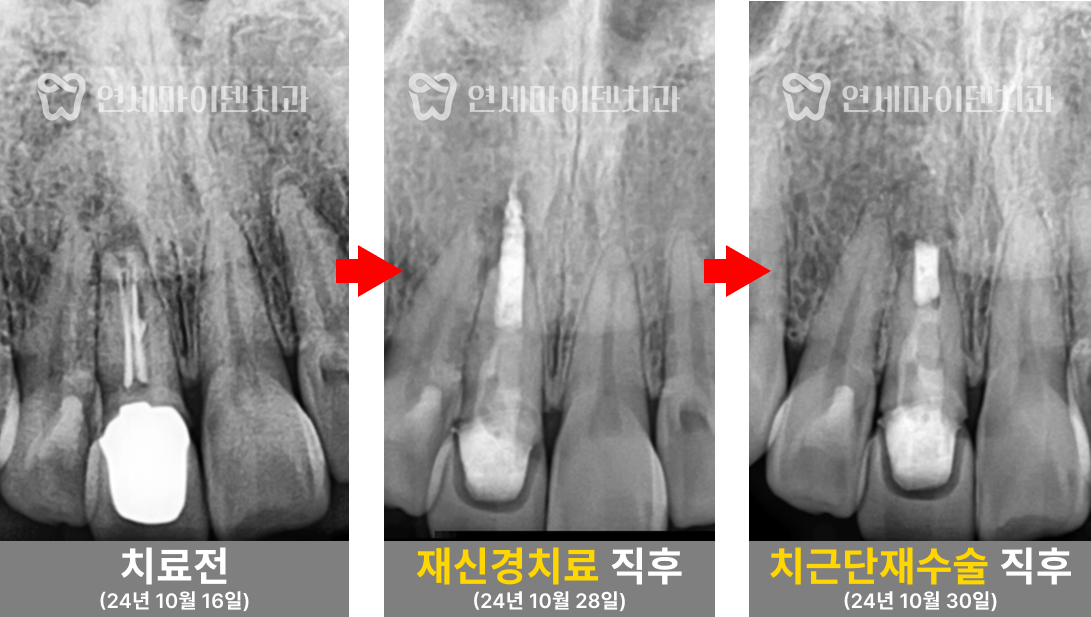

■ #25번, 첫 번째 치아 치료 - 재신경치료

살펴보니 과거에 받으셨던 신경치료의 퀄리티가 아쉬운 부분이 있었습니다.

신경관뿌리까지 치료가 되어있지 않고, 중간에 갭이 보였습니다.

치료를 조금만 하면 개선의 여지가 있겠다는 생각이 들어, 우선은 재신경치료를 하기로 했습니다.

그리고 앞쪽 치아의 신경치료 방식을 보니 거타포차 콘(GP cone)을 하나씩 삽입하는 오래된 방식으로 이뤄져 있었습니다. 오래된 방식이라고 반드시 나쁜 것은 아닙니다. 다만 현재 훨씬 개선된 치료법이 존재하기 때문에 환자분들께서 더 완성도 높은 치료를 받으실 수 있습니다.

거타퍼차 콘(GP cone)을 하나씩 꽂는 방식이 아닌, 수직 가압 충전법을 사용하여 거타퍼차 콘을 녹여 충전하는 현대적 방식으로 진행하였습니다. 레진 충전시에도 임시 재료 없이 원칙적인 치료로 진행했습니다.

앞쪽 작은 치아는 재신경치료를 잘 마무리 했으나, 뒤쪽 치아는 기존 보철을 제거하자 안쪽에서 계속해서 피가 나오는 상황이었습니다.